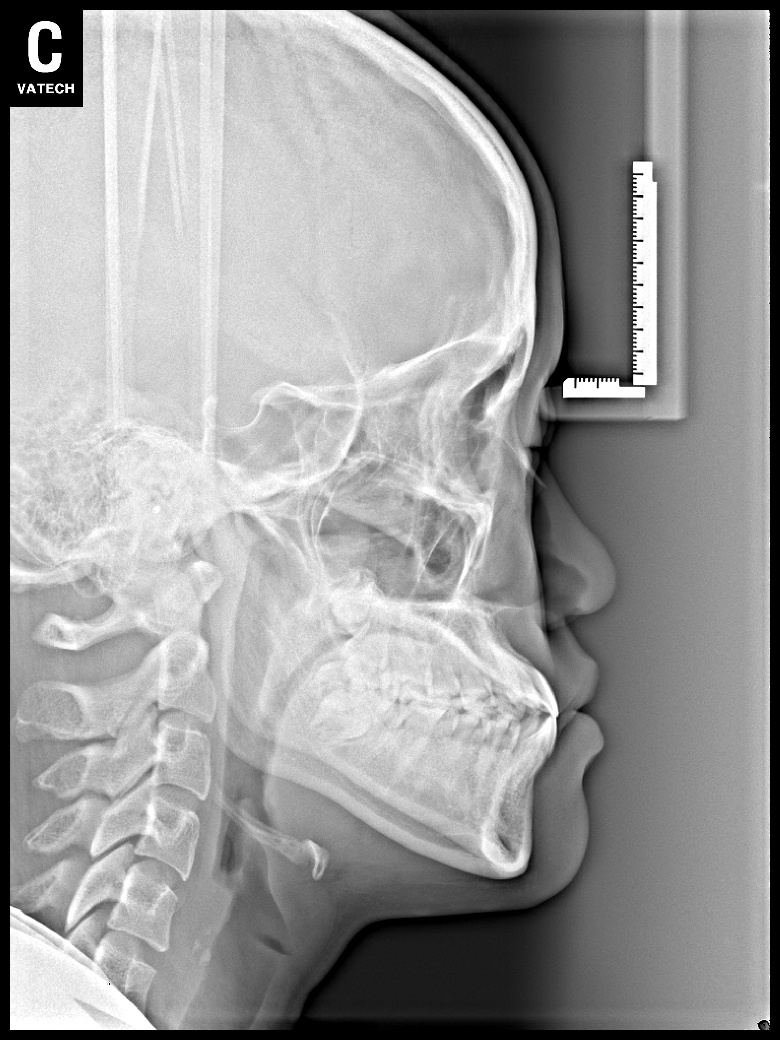

치료 전 사진입니다.